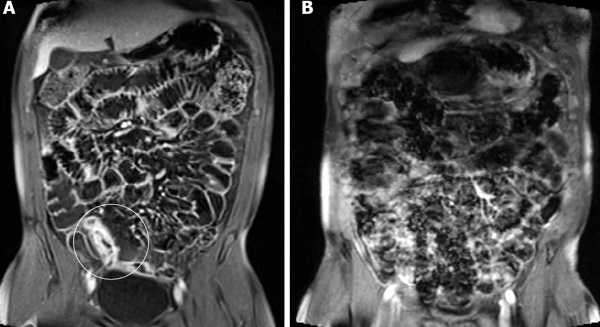

Для визуализации инвагината проводится УЗИ брюшной полости: определяется гипоэхогенное образование с участком гиперэхогенности в центральной части. Также может применяться ультразвуковая допплерография с целью оценки кровотока в сосудах брыжейки. Обзорная рентгенография брюшной полости обладает меньшей чувствительностью при обнаружении инвагината, но применяется как скрининговый метод исследования при острой боли в животе с целью исключения перфорации, обструкции.

Рентгенологические признаки могут быть весьма разнообразными: аномальное распределение газов, наличие уровней жидкости, расширение петель кишечника, пустые участки кишечника в области инвагината, а также кольцевидные чередующиеся участки затемнения и просветления. Более информативна рентгенография с контрастированием: определяется препятствие на пути контраста в виде полукруга или распределение бария наслаивающимися кольцами. С целью выяснения механических причин развития патологии может использоваться компьютерная томография.